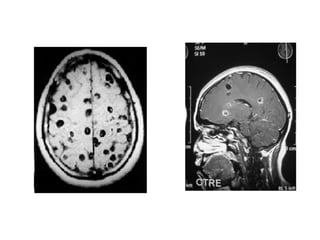

IRM

• Quistes vesiculares= lesiones redondeadas, señales

similares al LCR en T1 y T2 con escolex= nodulo

hiperintenso

• Quistes coloidales = T2 Hiperintensos con

respecto al parénquima, con edema y con cápsula

hipointensa con captación anular del contraste

• C. Granulares= Areas sin señal en t1 y T2

rodeados de un halo hiperintenso= gliosis

perilesional.

• Encefalitis cisticercosa: T1 multiples lesiones hipointensas

diseminadas en elparénquima cerebral; t2 se tornan

hiperintensos y se rodean de edema difuso